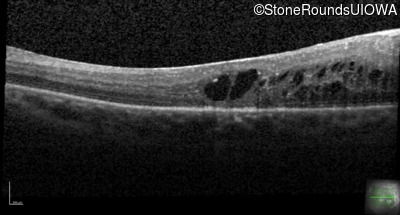

Age at visit: 43 years (Visit 2)

This 43 year old woman first experienced a slight loss of visual acuity at age 23. Fluorescein angiography at that time revealed some vascular leakage from the optic discs and peripheral retina. The maximum combined response of the ERG revealed a selective loss of the b-wave.